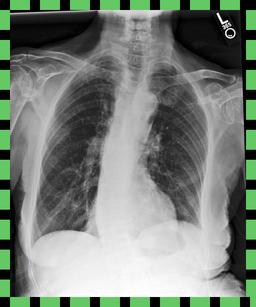

Curation of imaging datasets

CXR datasets [36] often contain multiple image acquisitions in a single visit due to data quality issues such as a limited field-of-view or scanning the wrong body part (Figure A.7). Unlike [9, 32, 81], we conduct curation to choose higher quality images among the potential candidates instead of performing a random selection. For this step, a separate BioViL-T is trained on ‘clean’ studies with single acquisitions and later used in a zero-shot setting to detect out-of-distribution samples [26, 27] arising from the re-imaging process. The candidate is selected as follows: for a margin . This approach is applied to enhance the quality of the temporal classification dataset given its limited size.

A.4 Data curation of imaging datasets

Large datasets often contain instances that are mislabelled or out of distribution [35]. We used BioViL-T to perform pairwise ranking of instances in MIMIC-CXR (Section 3.3, ) and selected representative examples found in the dataset. Our method is able to select the most appropriate image for a range of different image-acquisition or image-processing issues (Figure A.7).

We found that many lateral acquisitions in the dataset were unexpectedly labelled as frontal (Figure 7(a)). Some images contained only noise (Figure 7(b)), non-human samples (Figures 7(d) and 7(e)) or incorrect anatomy (Figure 7(g)). Often, acquisitions with an incomplete field of view (FOV) (i.e., the lungs are not completely visible) were repeated (Figure 7(c)). Lastly, post-processed images were detected by the algorithm such as contrast-enhanced scans (Figure 7(i)) that are not often used for diagnostic purposes in clinical practice.